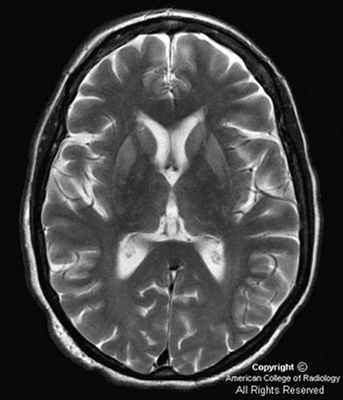

Болезнь Крейтцфельда–Якоба (БКЯ) является редким нейродегенеративным заболеванием, обусловленным накоплением патологической изоформы прионного белка. Классическая клиническая картина БКЯ характеризуется быстро прогрессирующей деменцией, атаксией, миоклонией, а также акинетическим мутизмом в терминальной стадии заболевания. Из инструментальных методов исследования ведущая роль в клинической практике принадлежит магнитно-резонансной томографии головного мозга. С 2014 по 2019 г. в Республике Саха (Якутия) авторы наблюдали 4 пациентов с вероятной БКЯ. У всех пациентов были примерно одинаковые возраст дебюта заболевания (50–60 лет) и начало с неспецифических церебральных симптомов. Однако последующее развитие быстро прогрессирующей деменции и других характерных признаков позволило предположить БКЯ. У пациентов выявлены показательные нейровизуализационные признаки в виде гиперинтенсивности хвостатых ядер и подушек таламуса в режимах FLAIR и DWI с образованием типичного сигнала «хоккейных клюшек», а также гиперинтенсивность серого вещества в режиме DWI (симптом «ожерелья Венеры»). У 3 пациентов заболевание закончилось фатально в течение года после его дебюта. Четвертая пациентка находится под домашним наблюдением (длительность заболевания 6 мес).

До недавнего времени «золотым стандартом» верификации диагноза БКЯ являлась биопсия головного мозга, позволяющая выявить характерные изменения в мозговой ткани в виде мелких вакуолей в телах нейронов, из-за чего ткань мозга приобретает губчатый вид, пролиферации клеток глии при отсутствии признаков воспаления. При электронной микроскопии возможно обнаружение прионных палочек, являющихся патогномоничным признаком заболевания. Указанные морфологические изменения отмечаются в коре головного мозга, базальных ганглиях, мозжечке и верхних отделах ствола мозга. Однако в случаях БКЯ биопсия мозга не нашла широкого применения в клинической практике из-за инвазивности метода, сложности санитарной обработки оборудования и утилизации биоматериалов, связанных с высокой устойчивостью прионов, а также вследствие небольшого объема биоптата мозговой ткани, что может быть причиной ложноотрицательных результатов морфологического и иммуногистохимического исследования. Однако в настоящее все больше распространена МРТ диагностика данного заболевания, по причине выявления специфических изменений, наиболее информативными являются последовательность DWI.

Магнитно-резонансная томография позволяет получить качественные и контрастные изображения головного мозга пациента. Во время проведения МРТ выявляются участки повышенного сигнала, локализованные в подкорковых ганглиях и таламусах. Кроме того, магнитно-резонансная томография дает возможность успешно определять признаки атрофических изменений мозжечка, коры головного мозга и расширение желудочковой системы.